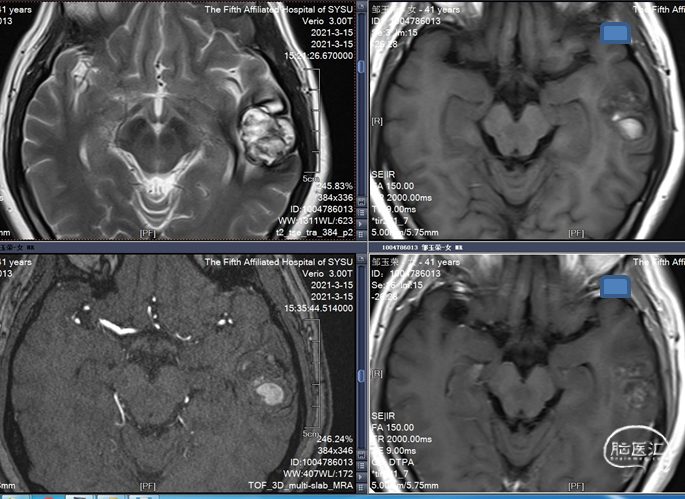

MRI 扫描:有边界,呈圆形。病灶在 T1 加权像呈等信号,在 T2 加权像或注射对比剂后呈高信号,病灶内有混杂低信号,病灶周围有环形低信号带。小型 (<1 cm) 以及非出血性海绵状血管瘤,磁敏感加权成像(SWI)的检出率更高。

病人出血两次,第一次出血采取保守治疗。第二次出突发疼痛来住院,做了导航下的微创手术,海绵状血管瘤边界清晰,可见明显黄染。手术过程顺利,止血彻底。术后两次病理检查发现海绵状血管瘤,第二次手术中发现明显团块,术后恢复良好。